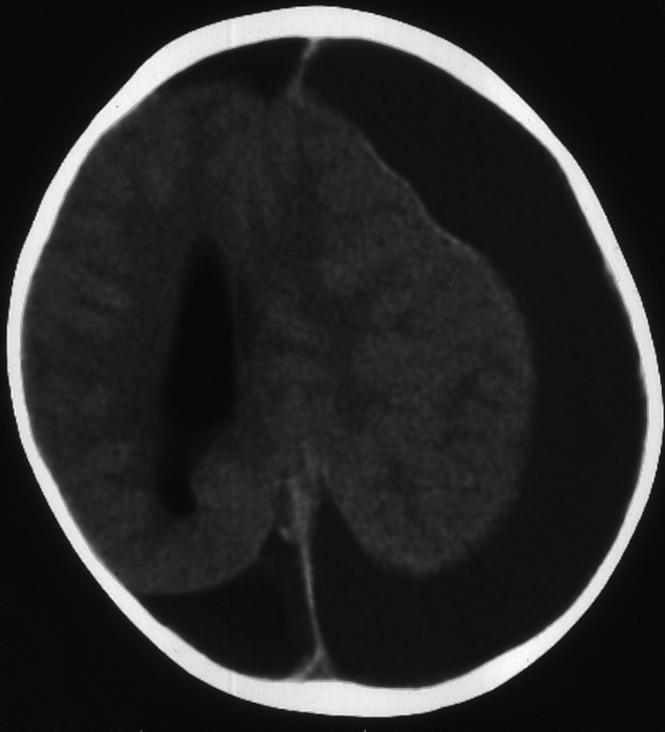

Severe complications that develop in the early stages in patients with acute leukemia have a mortal course. Bleeding, leukostasis, and less frequently, infections are responsible for early mortality. Hemorrhage is most common in acute leukemia and usually leads to death. Hemorrhage may occur due to chemotherapy or bone marrow transplantation in patients with acute leukemia. Leukocytosis, thrombocytopenia, sepsis, and coagulopathy increase the risk of bleeding. There may be multiple etiologic factors. Subdural or subarachnoid hemorrhage is less common than an intra-axial hemorrhage. The incidence of spontaneous subdural hematoma is higher in patients with leukemia. Although advances in the treatment of platelet transfusion and disseminated intravascular coagulation have decreased the incidence of hemorrhagic complications in patients receiving chemotherapy for acute leukemia, intracranial hemorrhage-related deaths are a significant problem. We discussed the etiology and management of chronic subdural hematoma detected in a two-year-old male patient with Acute Myeloid Leukemia and hyperleukocytosis.

急性白血病患者早期出现的严重并发症病程凶险。出血、白细胞淤滞,较少见的还有感染是早期死亡的原因。出血在急性白血病中最为常见,通常会导致死亡。急性白血病患者出血可能是由于化疗或骨髓移植引起的。白细胞增多、血小板减少、败血症和凝血病会增加出血风险。可能存在多种病因。硬膜下或蛛网膜下腔出血比轴内出血少见。白血病患者自发性硬膜下血肿的发生率较高。尽管血小板输注和弥散性血管内凝血治疗的进展降低了接受急性白血病化疗患者出血并发症的发生率,但颅内出血相关死亡仍是一个重大问题。我们讨论了一名两岁急性髓系白血病合并白细胞增多症男性患者中发现的慢性硬膜下血肿的病因及处理。